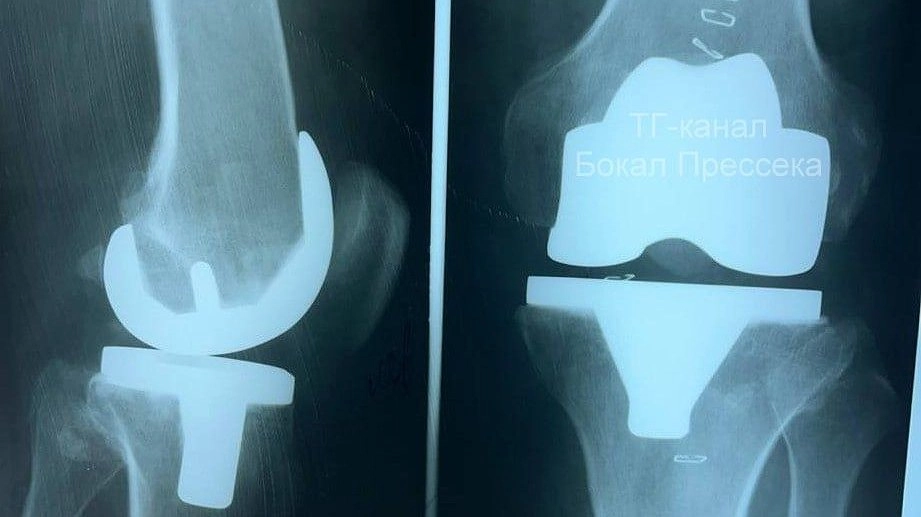

Первое эндопротезирование коленного сустава провели в нижегородской ГКБ №13

Эндопротезирование коленного сустава впервые провели в больнице № 13 Нижнего Новгорода. Об этом рассказал редактор «Стационар-пресс» Алексей Никонов в своем Telegram-канале.

Операцию провели 59-летнему мастеру спорта по боксу, который повредил колено. Эндопротезирование прошло успешно, и пациент уже самостоятельно передвигается на костылях.